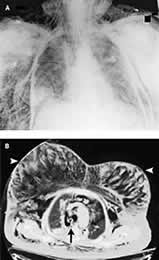

1例77岁妇女接受T12至S1椎板切除术和后脊柱融合术,手术取俯卧位,手术结束后改为仰卧位,送入重症监护病房,此时病人气道压力快速升高,出现大块皮下气肿和低氧血症。胸部X线显示有皮下气肿,但无明显气胸(图A)。放置双侧胸导管但病人的低氧血症无改善。CT扫描显示有大量皮下气肿(图B),并确认在气管隆突上2 cm(箭头)有一气管穿孔,与纵隔积气和气胸相关。推测此气管穿孔由气管插管所致,它易于发生在从俯卧位变为仰卧位时。病人随后接受了胸廓切开术,修复气管损伤,此后病人康复。